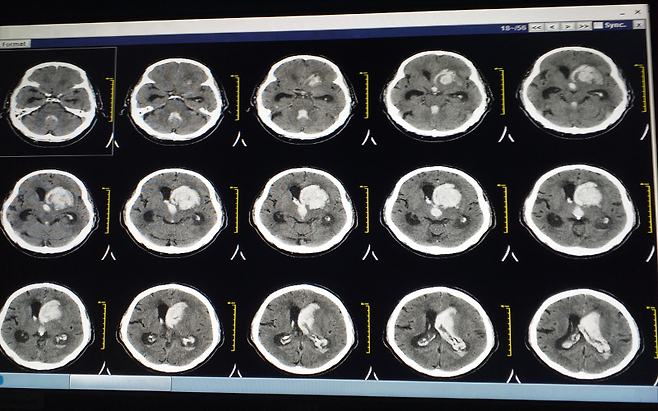

뇌출혈은 뇌혈관이 터지면서 출혈이 발생하는 질환입니다. 특히 고령일수록 혈관이 약해져 발생 위험이 높아집니다.

문제는 발생 속도가 매우 빠르다는 점입니다. 몇 분 사이에 상태가 급격히 악화될 수 있습니다. 치매처럼 서서히 진행되지 않기 때문에 더 위험합니다.

갑작스러운 심한 두통, 구토, 의식 저하, 한쪽 마비 증상이 나타나면 즉시 병원으로 가야 합니다. 지체할수록 뇌 손상이 커질 수 있습니다.